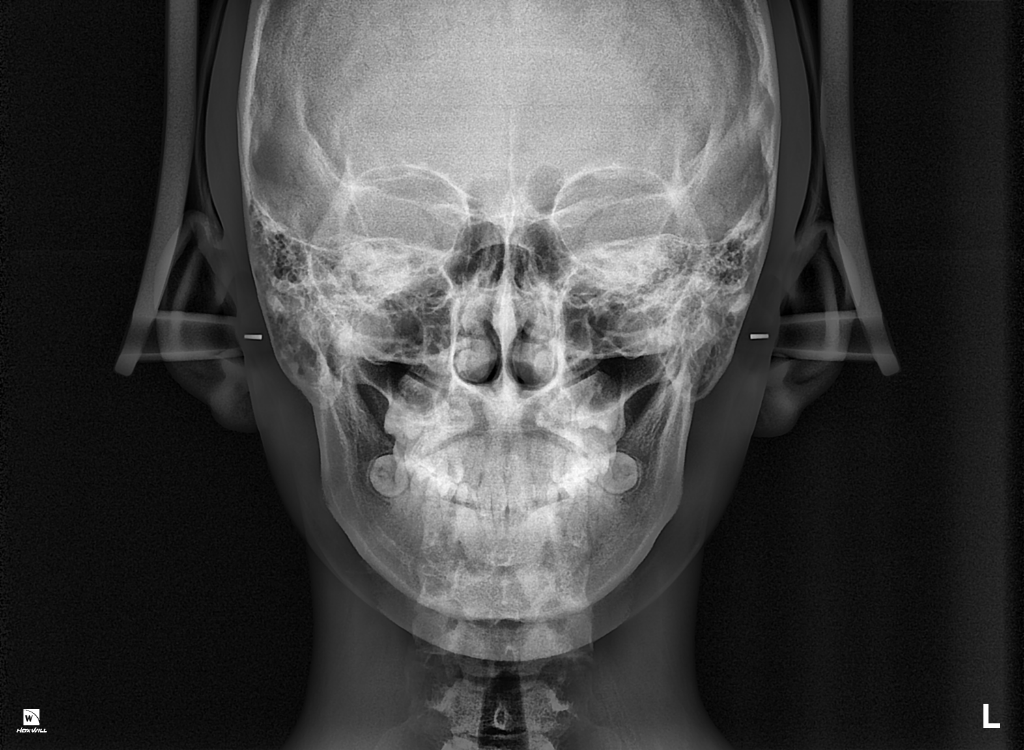

위, 아래 어금니가 맞물리는 상태를 보면 II급 부정교합의 상태이고 위 앞니가 아래 앞니를 정상보다 조금 더 많이 덮고, 더 튀어나온 것 같습니다.

돌출된 앞니는 외상 시 충격을 좀 더 받을 가능성이 높고요, 현재 어금니가 맞물리는 II급 부정교합의 형태가 치아가 정상적으로 맞물리는 것에 영향을 주어 치아가 보통보다 빠르게 마모될 수도 있고 파절될 수도 있습니다. 이러한 교합상태는 턱관절에 긴장을 불러일으켜 턱관절 질환, 안면비대칭을 유발할 가능성도 있습니다.